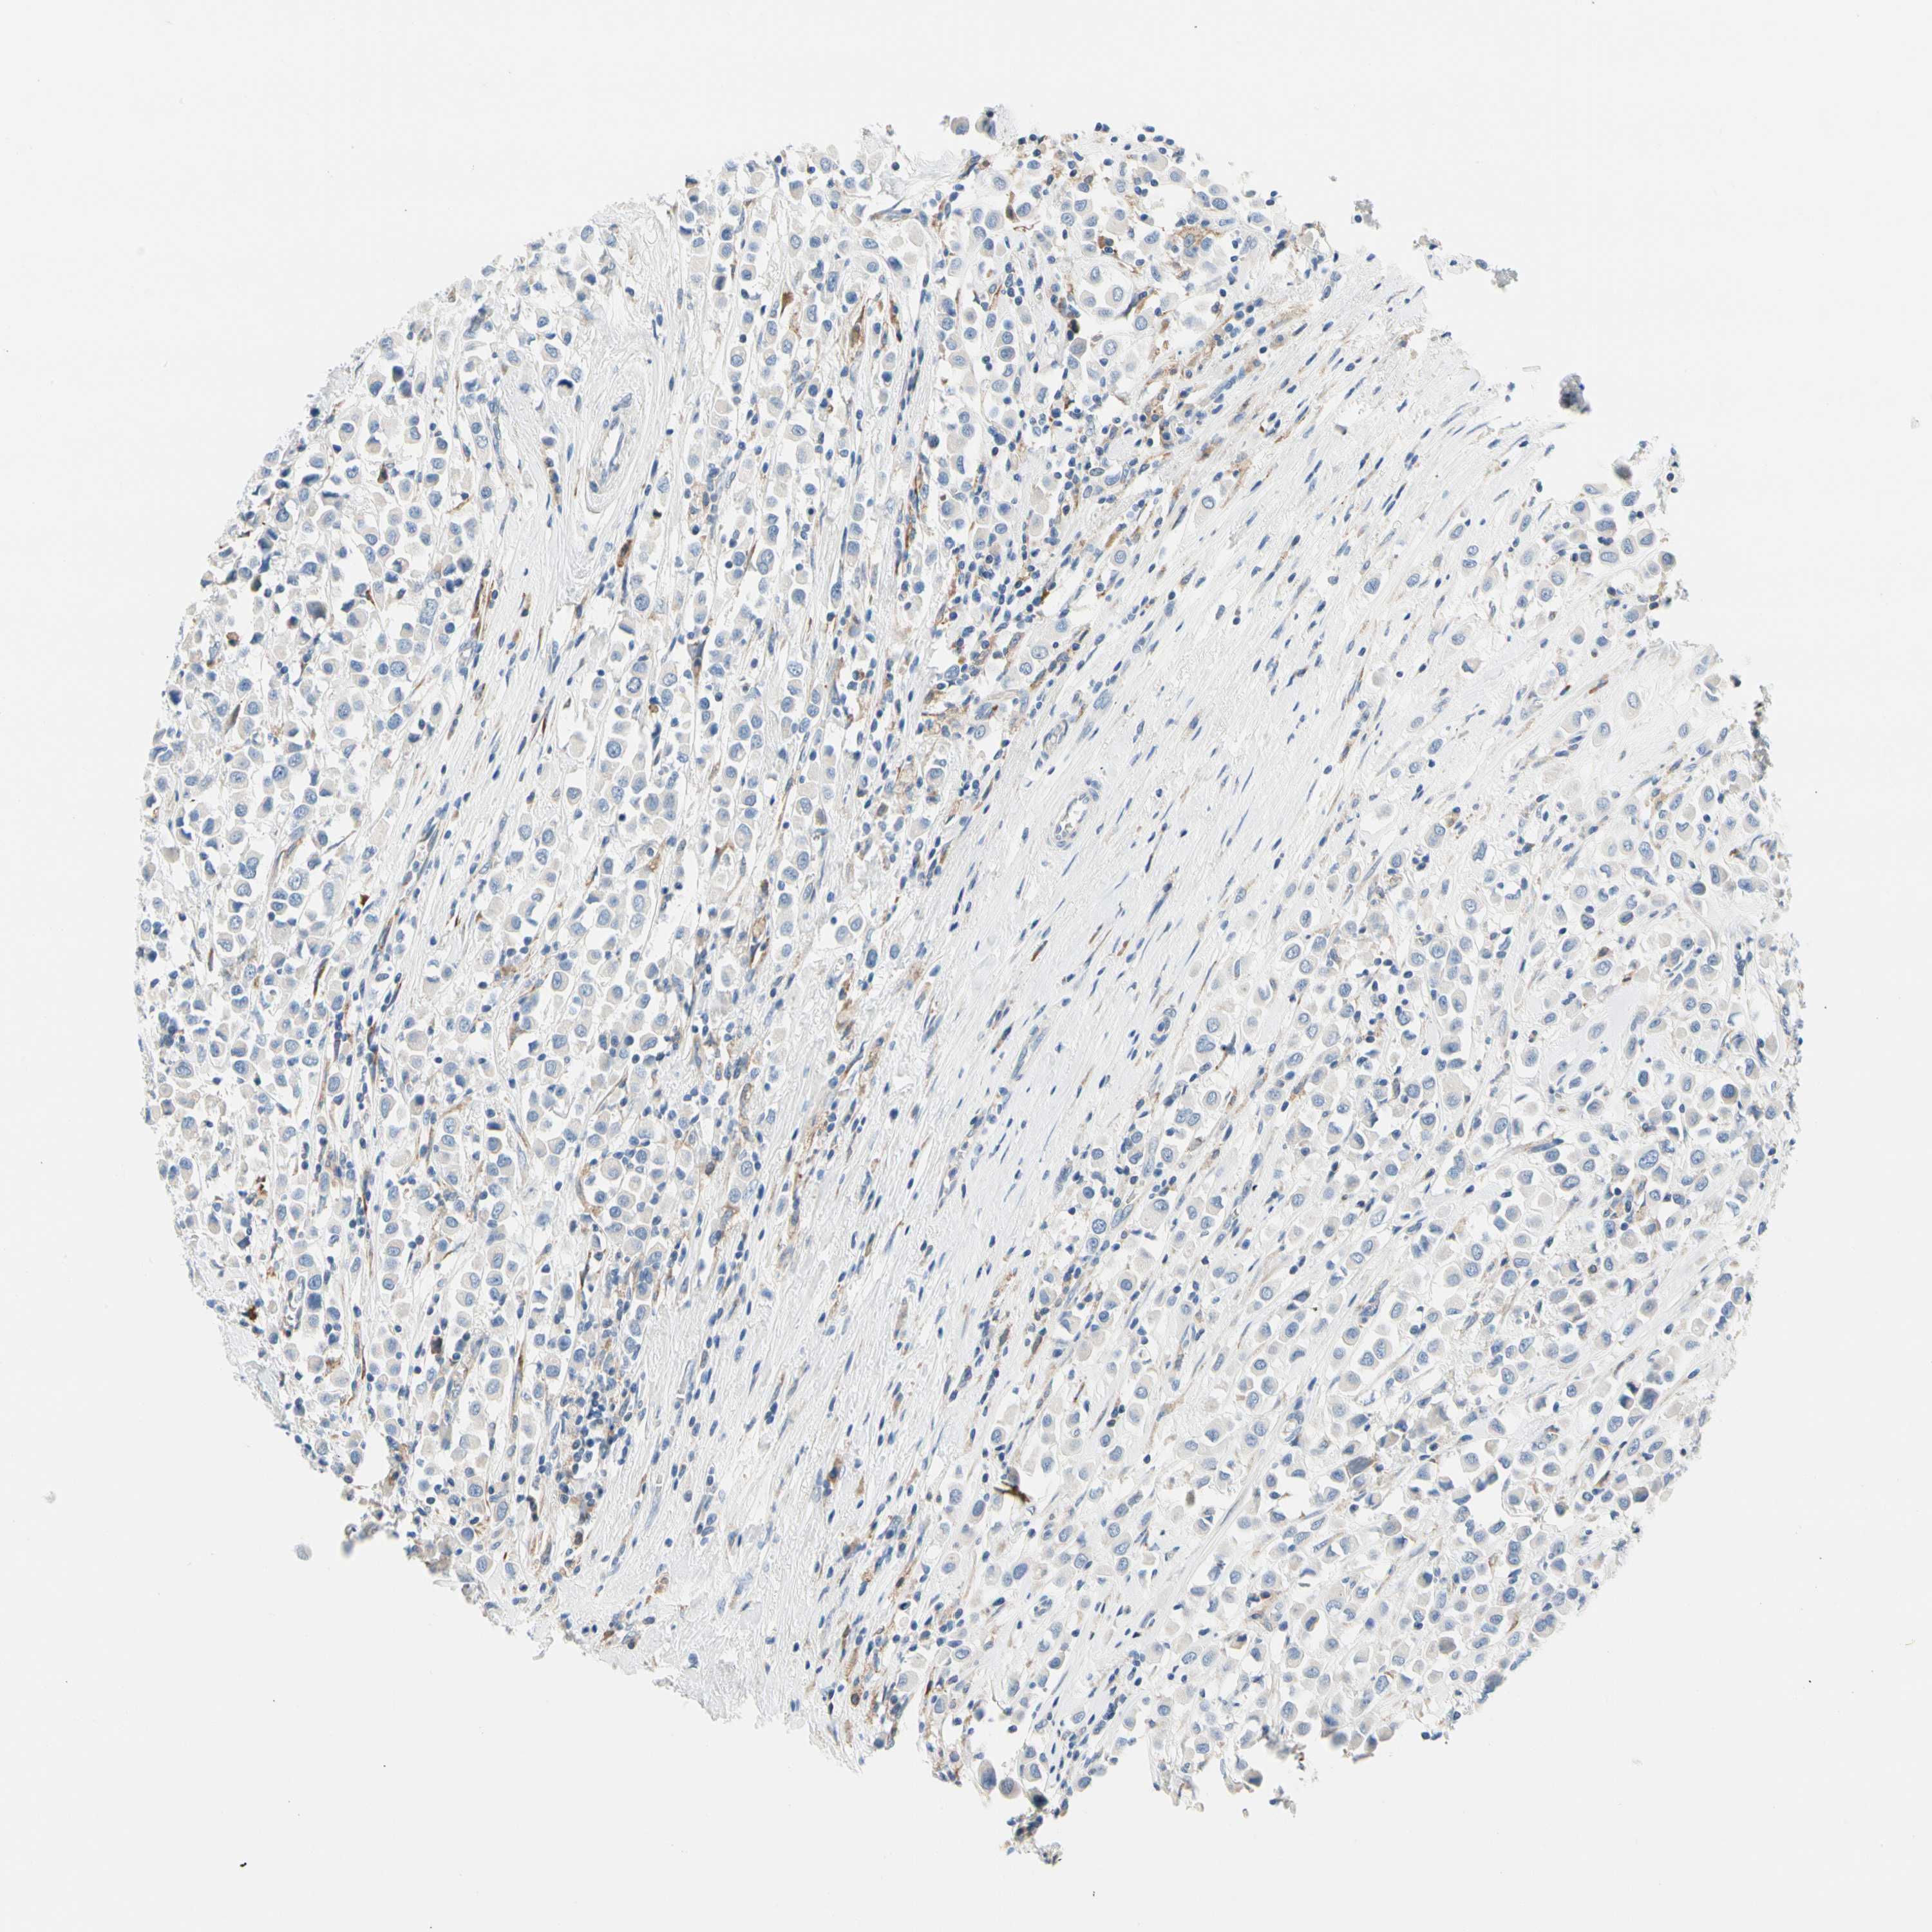

CANCER BREAST CANCER Show tissue menu

BRCA TCGA BRCA VALIDATION PROTEIN EXPRESSION